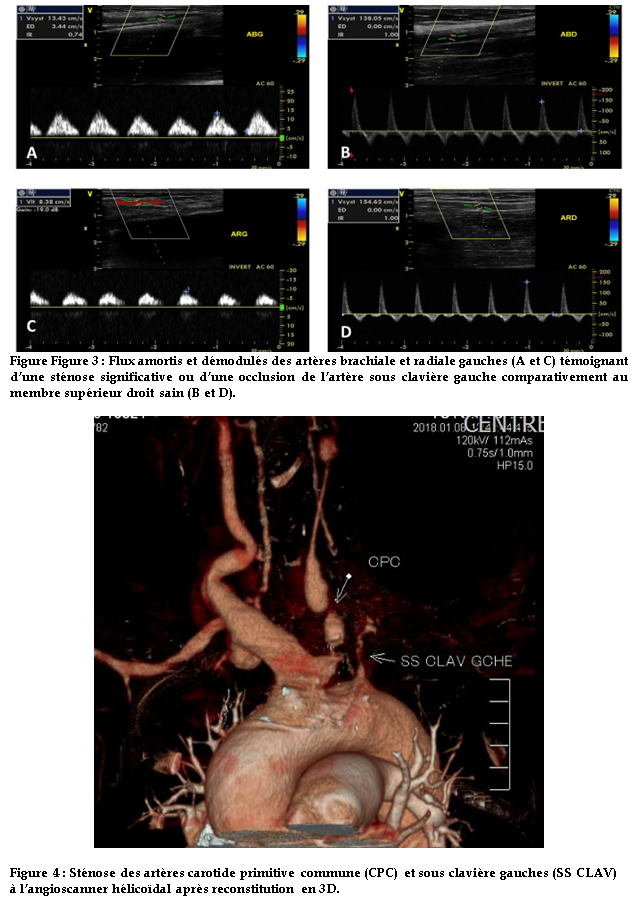

Il y avait par ailleurs à l’écho doppler des membres supérieurs, une sténose significative de l’artère sous clavière gauche à son origine responsable d’un amortissement et d’une démodulation des flux d’aval (figure 3).

L’angioscanner hélicoïdal centré sur les structures cervicales après reconstructions MPR et 3D confirme les sténoses des artères carotides et de la sous-clavière gauche (figure 4).